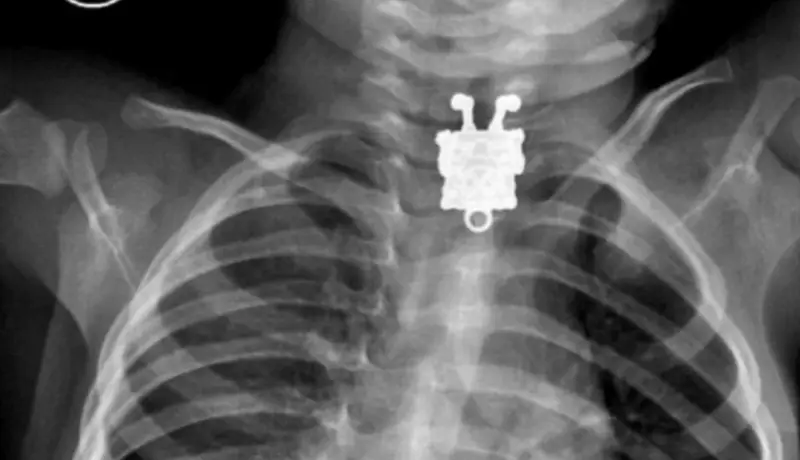

#6 Dieťa prehltlo postavičku SpongeBoba